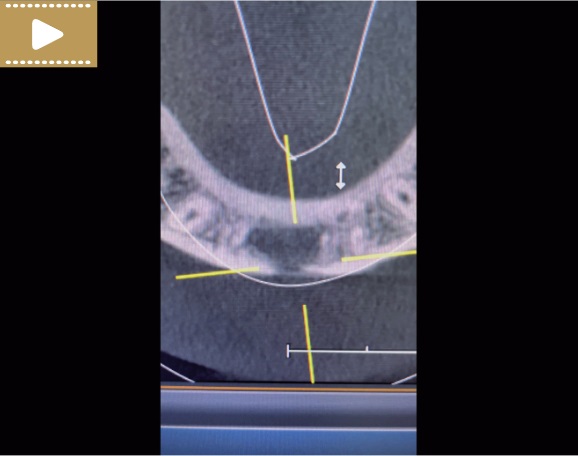

Film 2. CBCT przekrój osiowy, zęby 31 i 41 (kwiecień 2021 r.).